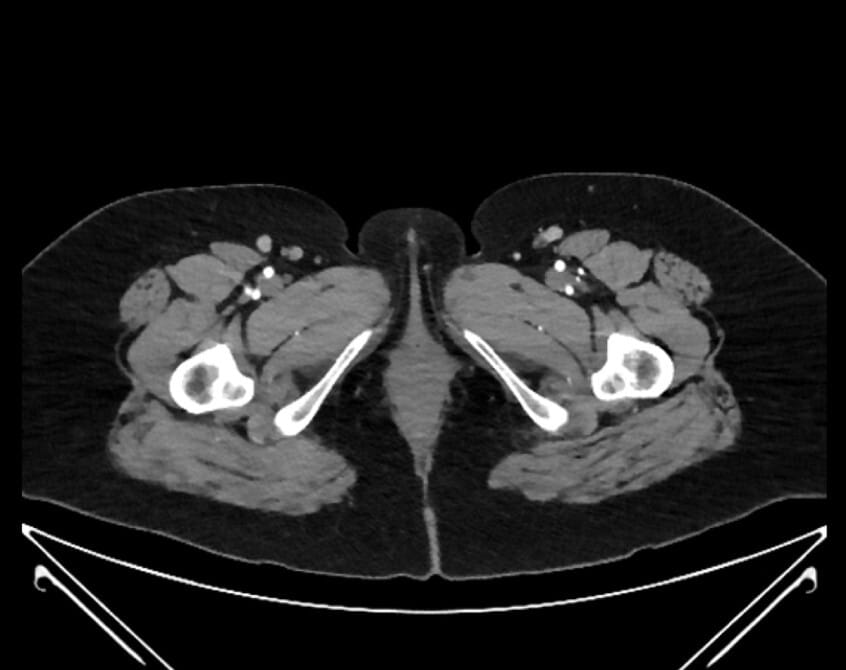

77. internal pudendal artery in pudendal canal

78. inferior rectal artery

79. muscular perforator branch of profunda femoris artery

80. superficial femoral artery

81. profunda femoris artery